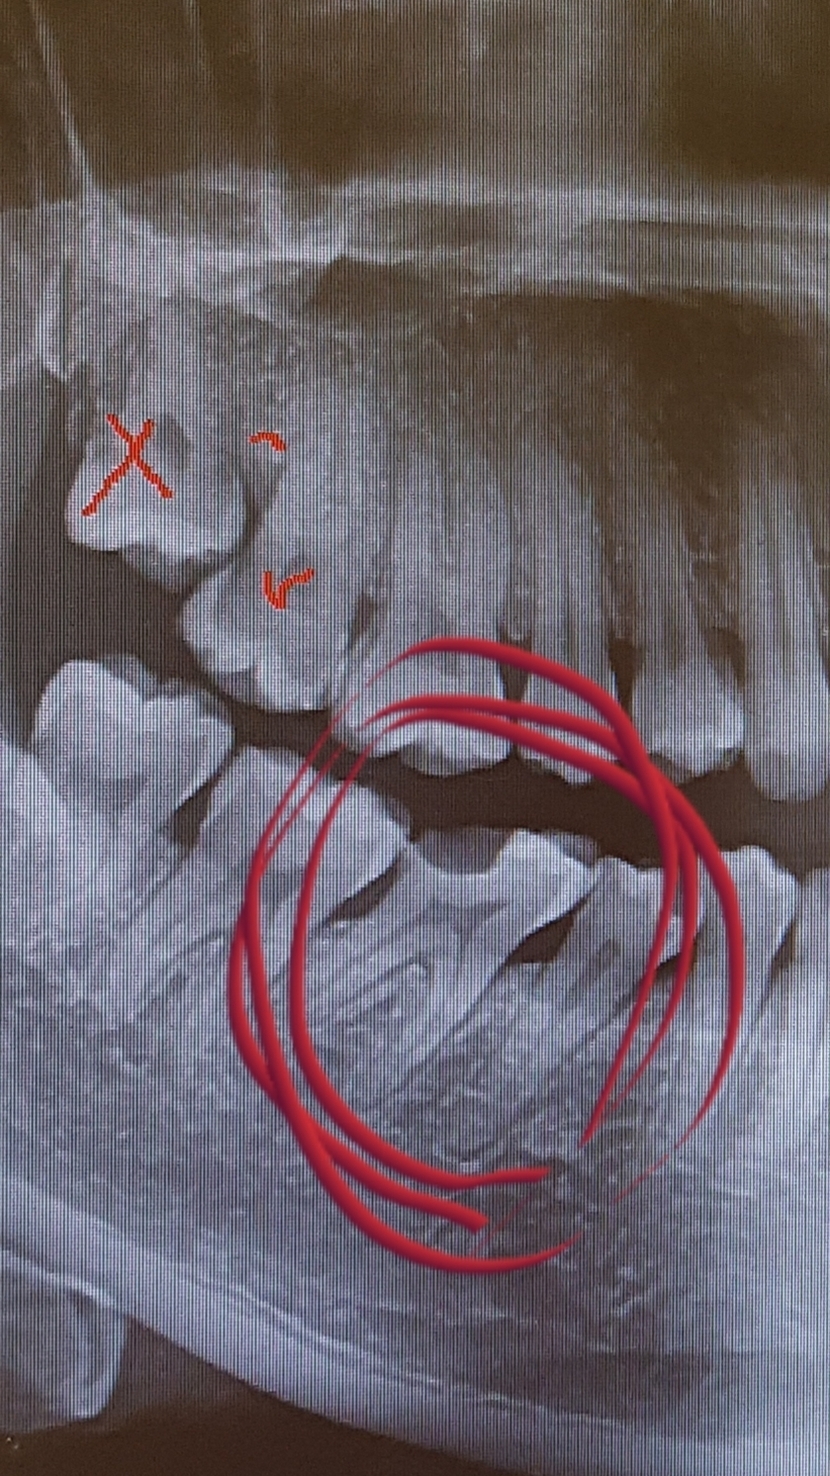

어금니가 깨져 치과갔더니 금으로 때우자 하는데

비용이 40이라네요

또 때울부분도 넓어서 글타고,